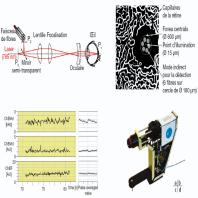

- eFig. 9-27 - Principe du fluxmètre laser Doppler de la tête du nerf optique

- eFig. 9-28 - Méthode entoptique du champ bleu